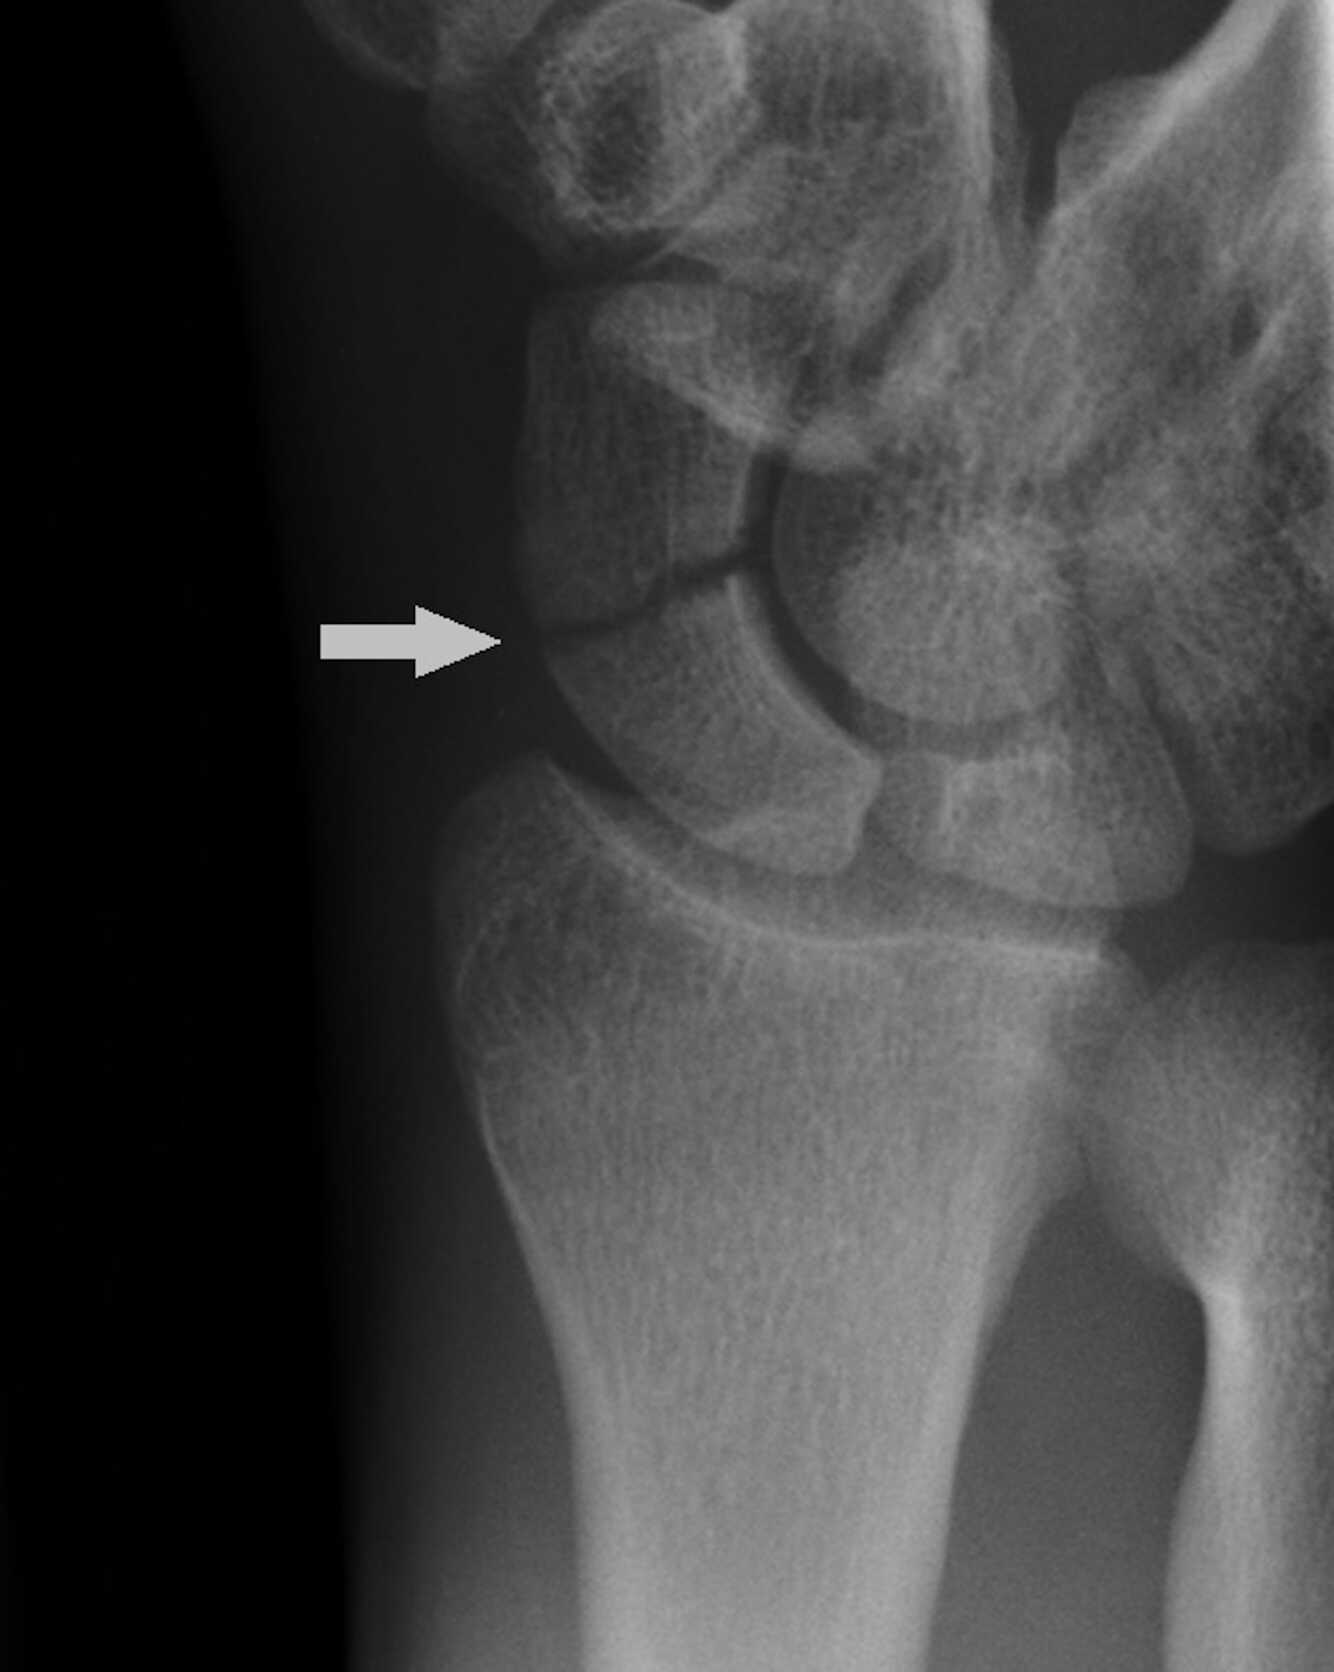

vad menas med scaphidoeumfraktur?

vanligt? vem? läcker hur?

A

Båtbensfraktur

Scaphoideumfraktur är den vanligaste carpala frakturen och utgör ca 60-70% av alla karpalbensfrakturer och är vanligast förekommande bland unga individer.

Dålig blodförsörjning, fr.a. den proximala tredjedelen plus stor rörlighet gör frakturen svårläkt.

14

Q

behandling av båtbensfraktur?

beroende på rtg svar

• neg rtg ==> schap gips och sedan kontroll rtg 2v

• odislocerad fraktur - gips 3 månader

• dislocerad fraktur - op med öppen reposition

How well did you know this?